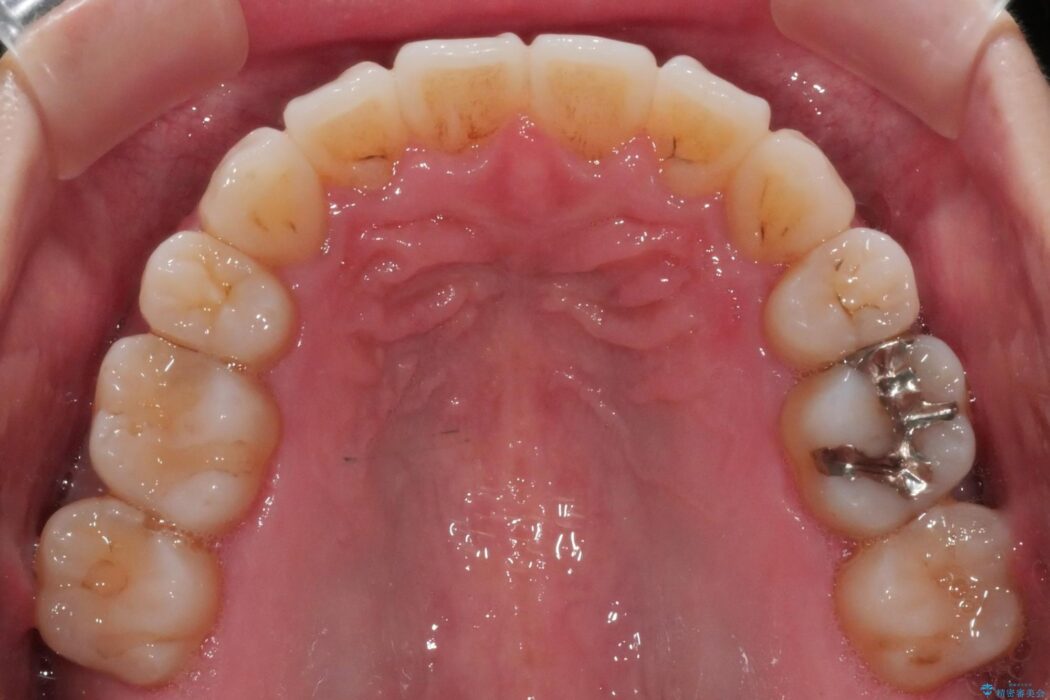

抜歯矯正後の上の前歯の後戻りが気になるとご来院された患者様です。

インビザラインモデレートで治療が可能と診断し、矯正治療を行いました。

歯と歯の間を削るのと、歯列のU字型のアーチを僅かに外側に広げる事でスペースを作り、前歯の角度の改善をしました。

保定装置は、マウスピースと前歯の裏側を細いワイヤーで固定(ボンディングリテーナー)を併用していただいてます。